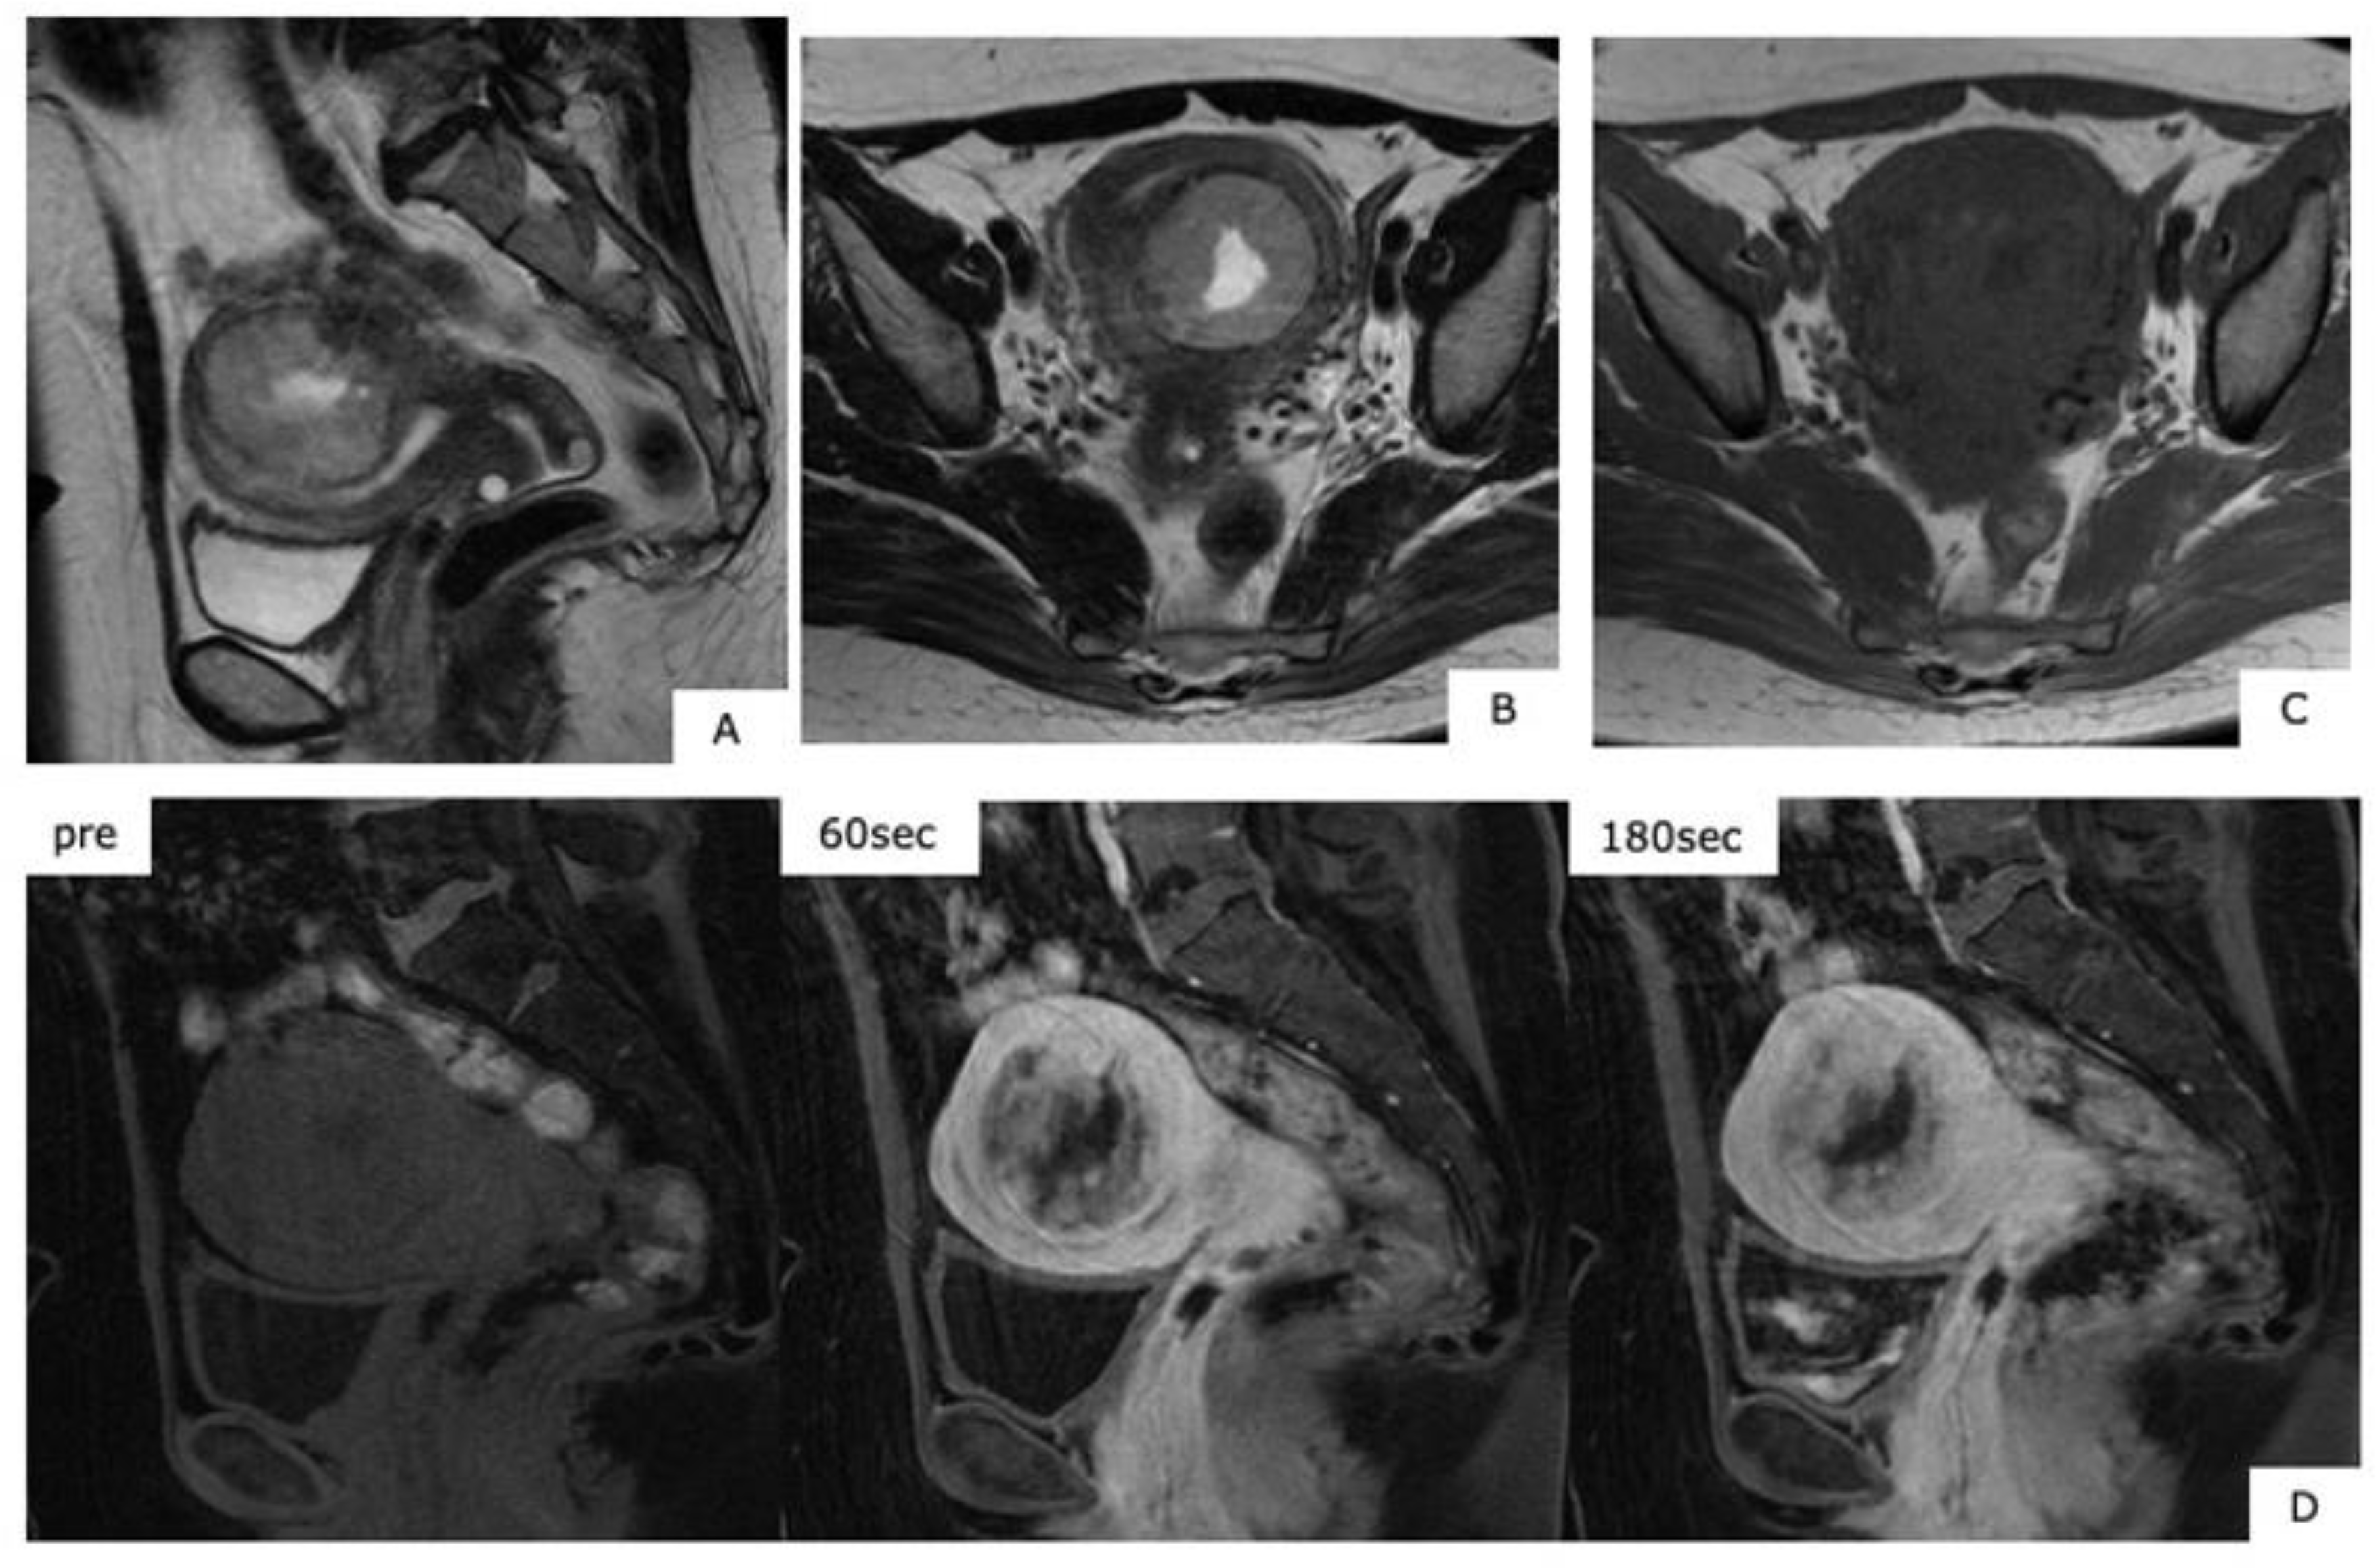

An MRI scan is useful in differentiating between uterine myoma and sarcoma because a typical MR image for myoma exists. That is, uterine myoma shows a clear border, with a mostly spherical shape. In T1WI, there are more equivalent signals or relatively low signals compared to those for normal muscle layer, and in T2WI, mass is depicted in signals that are patently lower than those for normal muscle layer (Figure 1). Confirmation of an MR image enables the diagnosis of myoma. However, when the modification of degeneration is added to a myoma, a completely different image finding is presented than the above-described typical one (Figure 2). Subsequently, the differentiation of such a myoma from uterine sarcoma becomes problematic.

Figure 2.

MR images of degenerated leiomyoma. These images always require a differential diagnosis from sarcoma. (A): hyaline degeneration (T2WI), (B): leiomyoma with cystic change (T2WI), (C): cellular leiomyoma (T2WI), (D): red degeneration (T1WI), (E): myxoid degeneration (T2WI).